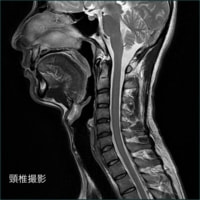

軟部組織のコントラストに優れ、様々なコントラストパラメーターを有するMRIは、頭頚部、体幹部、脊椎・脊髄、整形領域、心臓領域とほぼ全身に渡る断層画像をあらゆる角度で撮像できます。

当院導入のGE社は超伝導MRIの稼動実績において、日本だけでなく世界においてもトップシェアを維持し続けて、良質な画像を得ることが出来ます。

当院のMRIの特徴

今回当院では画像描出に定評のあるGE社の1.5TのMRIを採用しました。

この装置は光デジタル伝送技術を採用し、外部ノイズの混入を抑え、劣化のない高画質な画像を得ることができます。